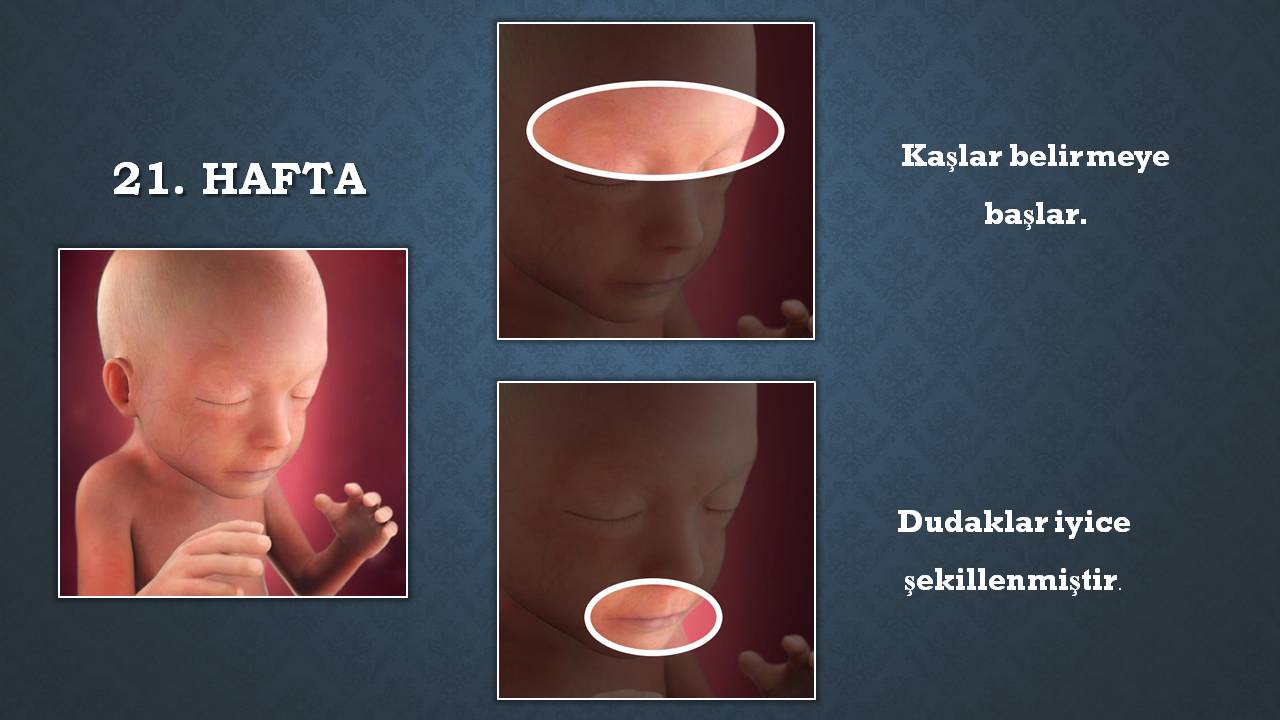

Hafta hafta fetus ne yapar? Prof. Dr. Başak Baksu From Pinterest

Hafta hafta fetus ne yapar? Prof. Dr. Başak Baksu From Pinterest

Hafta hafta fetus ne yapar? Prof. Dr. Başak Baksu

Hafta hafta fetus ne yapar? Prof. Dr. Başak Baksu